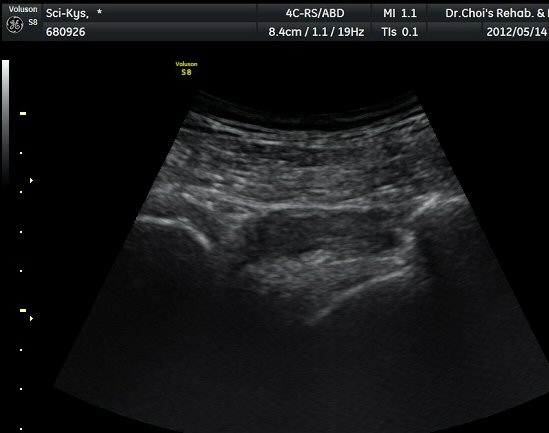

¾ûµ¢ÀÌ Á°ñ¿¡¼­ Á°ñ½Å°æ Ⱦ´Ü¸é°Ë»ç¿¡¼­ ´ëµÐ±Ù°ú quadratus femoris »çÀÌÀÇ ±Ù¸·

°æ°èºÎ¿¡¼­ Á°ñ½Å°æÀÌ °üÂûµÇ´Âµ¥ ³»Ãø Á°ñ°áÀý(ischial tuberosity) ÃøÀ¸·Î Ä¡¿ìÃÄ

ÀÖ´Â °ÍÀ¸·Î ÆÇ´ÜµÈ´Ù(±×¸² 1, 2, 3).

Á¤»óÃø(±×¸² 6, 7)°ú ºñ±³Çϸé Á°ñ½Å°æÀÇ ³»Ãø ÀüÀ§°¡ ¶Ñ·ÈÇÏ´Ù.